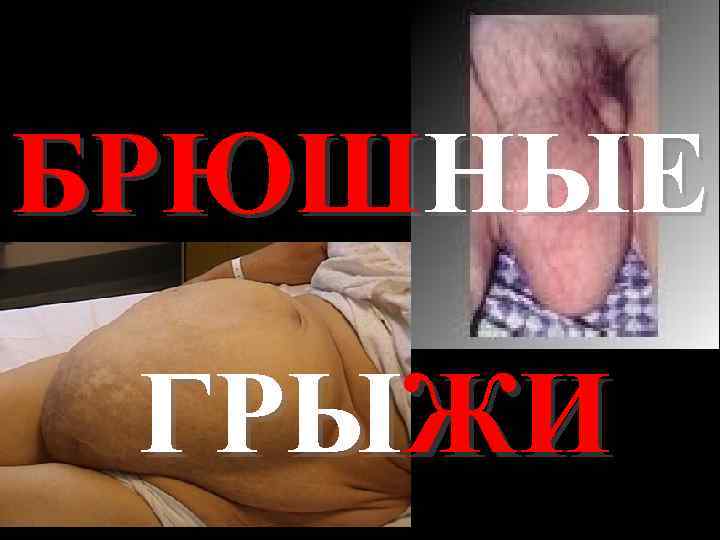

БРЮШНЫЕ ГРЫЖИ

• Наружные грыжи живота встречаются у 7% населения • Грыжесечение занимает второе место после аппендэктомии, составляя 15% (700 000 грыжесечений в год)